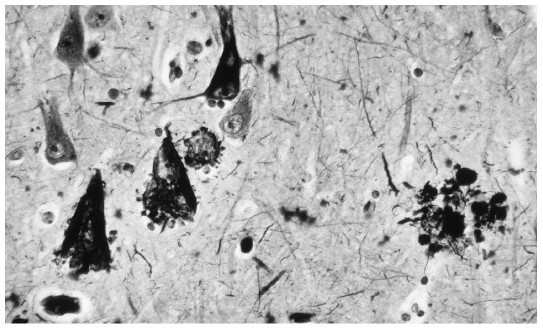

现在,我们知道阿尔茨海默氏病患者存在海马、大脑皮层和其他脑区域的神经原纤维缠结(neurofibrillary tangles,NFT;神经元内蛋白质纤维缠结)和脑老年斑(cerebral senile plaques,SP;神经元细胞间β-淀粉样蛋白沉积)(Chapman et al.,2006;Morris,2006)。正常衰老都会伴随NFT和SP的增加,但阿尔茨海默氏病患者数量更多。解剖学证据显示当前对该病诊断的准确率为90%(Morris,2005)。

一个对阿尔茨海默氏病患者脑组织的显微检查揭示了与该病有关的神经原纤维缠结(左侧深色三角形状)和脑老年斑(淀粉状、右侧深色圆形状)。